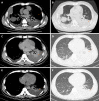

Case summary: A 46-year-old man was admitted for symptom of persistent abdominal pain, nausea, and vomiting for 2 d after heavy drinking. During hospital stay, he suddenly developed skin rash and a secondary fever. The laboratory findings revealed progressive pancytopenia, abnormal hepatic tests, and elevation of serum triglyceride, ferritin, and lactate dehydrogenase levels. However, apparent bacterial or viral infections were not detected. He was also possibly related to autoimmune diseases because of positive expression of various autoimmune antibodies and no remarkable past history. Finally, the bone marrow examination showed a histiocytic reactive growth and prominent hemophagocytosis, which resulted in a diagnosis of HPS. Unexpectedly, the patient responded well to the immunosuppressive therapy.